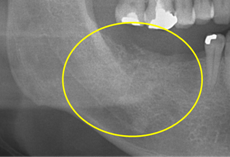

抜歯のう胞摘出

Perio Wave+Er:YAGレーザー+コールドレーザーで治療した箇所の経過です。

左から直後、1ヶ月経過時、2ヶ月経過時の画像です。

骨再生の確認をした際の動画です。

画像をクリックすると、youtubeにジャンプします。

骨再生

骨再生した箇所にインプラントを埋入します。

CTで治療計画を綿密に練ったうえで行いました。

インプラント埋入の際の動画です。

インプラント埋入

インプラント埋入後のレントゲン画像です。